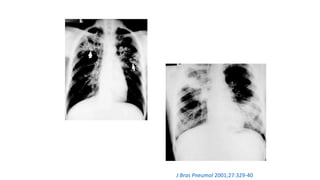

J Bras Pneumol 2001;27:329-40

J Bras Pneumol 2004;30:S 3-85

Baum´s Text Pulm Dis 5th ed